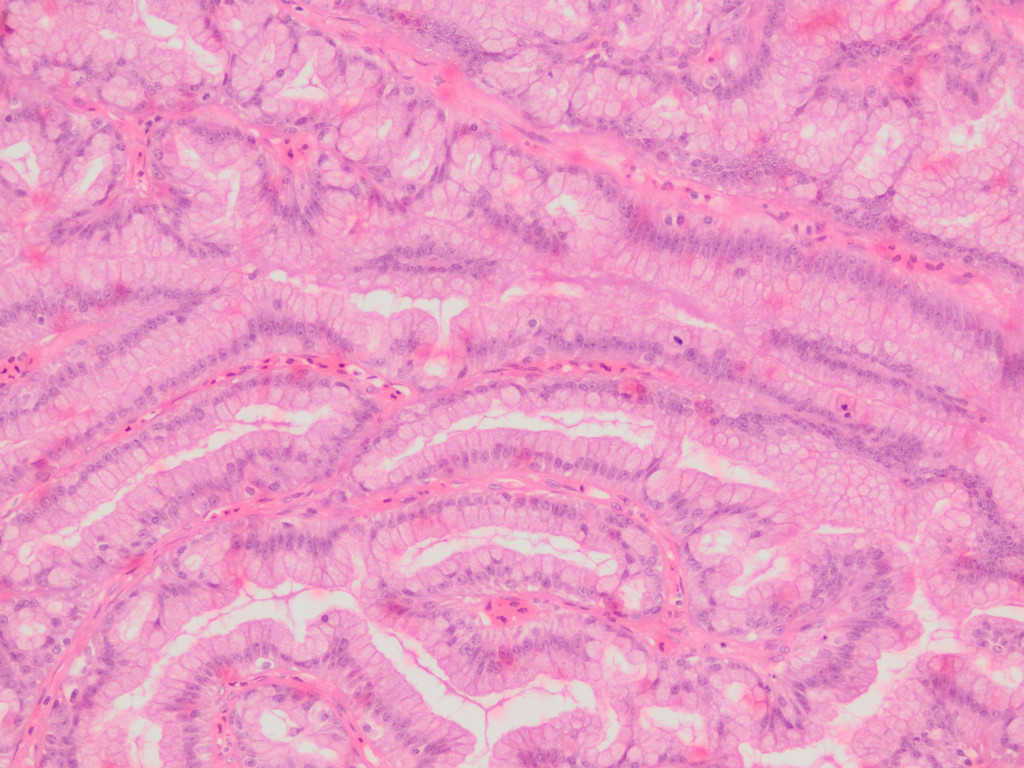

Новообразование сформировано многочисленными папиллярными выростами разного размера и формы с эпителиальными канальцами, разделенными и поддерживаемыми обильной фиброзной стромой. Над поверхностью эпителия отмечается накопление большого количества муцинозного секрета. На периферии образования обнаруживаются небольшие участки эпителиальных клеток, формирующие мелкие гнезда, иногда заполненные кератиновыми чешуйками (фото 11-13).Неопластические клетки имеют кубическую или цилиндрическую форму, умеренное количество цитоплазмы, часто заполненной обильным количеством секреторного материала, который сдавливает ядро. Ядра пикнотичные или округлые, с мелкозернистым хроматином и округлыми малиновыми ядрышками. Количество митозов – 2 в 2,37 мм2. Обнаруживаются обширные участки скопления свободнолежащих эритроцитов. Строма иногда инфильтрирована немногочисленными клетками воспаления.

Морфологический диагноз: новообразование – карцинома слюнной железы, преимущественно папиллярного типа, низкая степень атипии и количества митозов, выраженная секреторная активность.